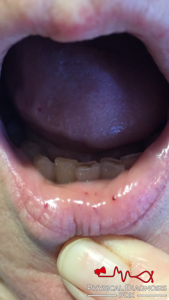

• Hereditary Hemorrhagic Telangiectasia